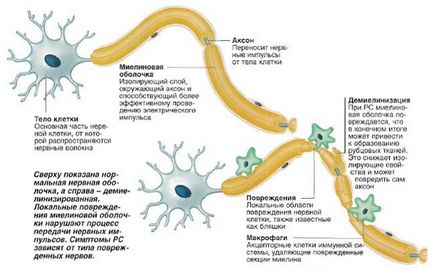

Sclerosis multiplex Központ található az agyban. Egy egészséges emberi agy és a gerincvelő borítja a vér-agy gáton, ami megvédi az agyat a penetráció a vérsejtek és a különböző mikroorganizmusok. A sclerosis multiplexben szenvedő betegek át a gáton áthatolni a limfociták - immunsejtek kialakítva, hogy a fertőzések leküzdésében. De kezdik támadni az agysejtek, tönkretéve a bőrük. A helyszínen a pusztítás van a gyulladás, amelyet azután helyébe kötőszövet. A kép a „sebhely”, hogy lesz egy funkcionális és megzavarja az ingerület az agy a test. Ennek eredményeként egy személy lehet zavart beszéd, csökkent érzékenység, a test kontroll nehézzé válik.

A betegség nagyon hosszú lappangási idő, hogy tarthat több héten át több éven át. Funkciók befolyásolja az immunrendszer sejtjei az agy, hogy gyorsan hozza a szomszédos sejtek és a károk nem észrevehető. Az első jelei a sclerosis multiplex észrevehetővé válik csak, ha az immunrendszer sérült Kolo 40 százaléka neuronokat. Alakult plakk tisztán látható a képen: